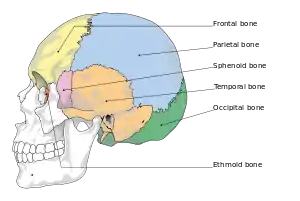

They typically require a significant degree of trauma to occur.[1] The break is of at least one of the following bones: temporal bone, occipital bone, sphenoid bone, frontal bone, or ethmoid bone.[1] They are divided into anterior fossa, middle fossa, and posterior fossa fractures.[1] Facial fractures often also occur.[1] Diagnosis is typically by CT scan.[1]

Diagram showing bones that may be involved in a basilar skull fracture

Basilar skull fractures include breaks in the posterior skull base or anterior skull base. The former involve the occipital bone, temporal bone, and portions of the sphenoid bone; the latter, superior portions of the sphenoid and ethmoid bones. The temporal bone fracture is encountered in 75% of all basilar skull fractures and may be longitudinal, transverse or mixed, depending on the course of the fracture line in relation to the longitudinal axis of the pyramid.[5]